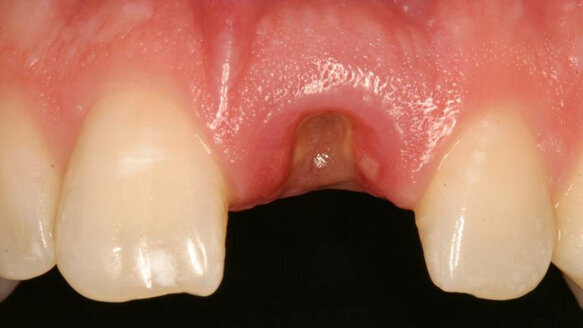

A medically and periodontally stable 37-year-old man presented with coronally fractured tooth #9, which had a history of endodontic treatment (Figs. 1a & b). The tooth was deemed restoratively hopeless.

After three months of uneventful healing (Fig. 4), Stage 1 implant placement was initiated.